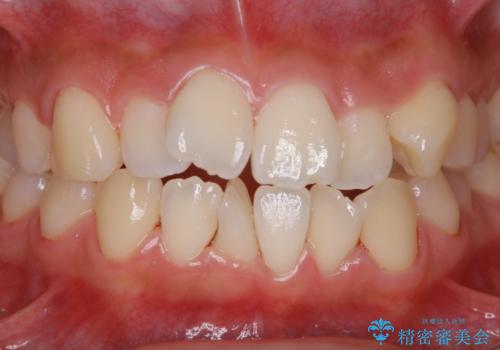

矯正治療開始前のPMTC

- 矯正カウンセリング、矯正検査後にクリーニング希望で来院されました。しばらく歯科医院にて、クリーニングを行ってなく、歯石やステインが気になるとのことでした。PMTC(自費クリーニング)30分コースを行いました。

矯正治療は、歯を動かすため歯ぐきにもかなりの負担がかかります。そのため歯列矯正の前にはしっかりとしたクリーニングを行い、歯ぐきのコンディションも整えることが大切です。また、歯石やステイン(着色)が歯についたままだと、矯正の装置が、適切に設置できなかったり、装置が外れやすくなってしまったりとトラブルの原因になることがあります。矯正治療中に歯周病や虫歯にならないためにも、専門的なクリーニングを行うことが大切です。